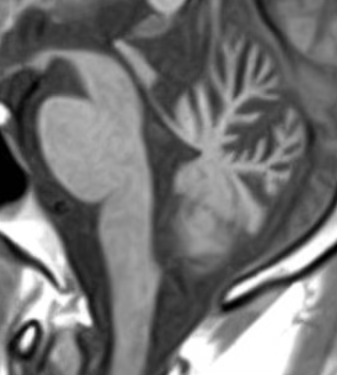

MRIにはいくつかの撮り方がありますが、

T1強調画像の矢状断とは、脳を横から見た断面の画像のことです。

ちょうど、体を左右に分けるようにスライスしたイメージで、

脳幹や小脳の形を一目で確認できるのが特徴です。

特に、脳の“厚み”や“縮み具合(萎縮)”が見やすいため、

神経の病気を考えるうえで重要なヒントになることがあります。

③ 小脳虫部が縮んでいるとき

前上部の虫部が強く萎縮し、

矢状断で「上虫部がえぐれた」ように見える場合

👉 アルコール性小脳変性症

をまず疑います

④ 小脳が全体的に縮んでいるとき

虫部と半球がバランスよく萎縮し、小脳全体が均一に薄くなる(皮質性小脳萎縮:CCA)場合

👉 脊髄小脳変性症(SCD)

を考えます